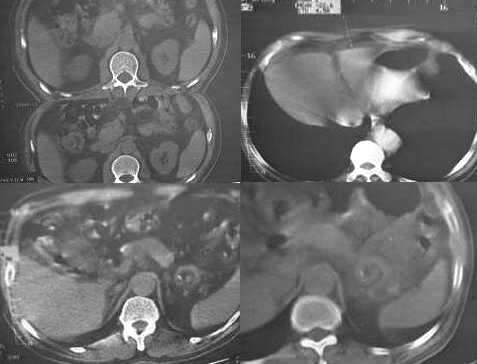

男,60岁,反复头痛,头昏,测血压最高240/120

临床怀疑嗜镉细胞瘤。做ct想了解肾上腺有无肿块。

疑问:1. 1185 1186 图 肝脏前缘低密度灶是否为腹水?ct值为-22——9.6

2.1187 图 是否为胃腔内寄生虫?还是其他呢?

3. 1167 1168 图 胆囊壁旁是什么结构?似乎不是胆囊壁增厚

3.肾上腺没有发现异常?

胆囊旁、肝脏前缘为运动伪影。胃内后方考虑肠管,建议此类检查前喝0.7%泛影葡安800ml后再扫描。